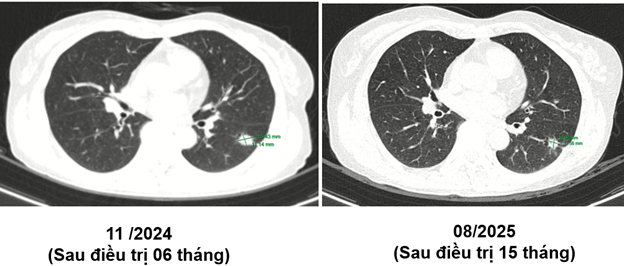

Ct ngực sau điều trị:

Theo dõi định kỳ bằng lâm sàng, chụp CT ngực và MRI sọ não sau 3 tháng, 6 tháng và 15 tháng cho thấy:

- Tổn thương phổi và não giảm kích thước rõ rệt.

- Không xuất hiện tổn thương di căn mới.

- Tình trạng toàn thân ổn định, chất lượng sống được cải thiện.